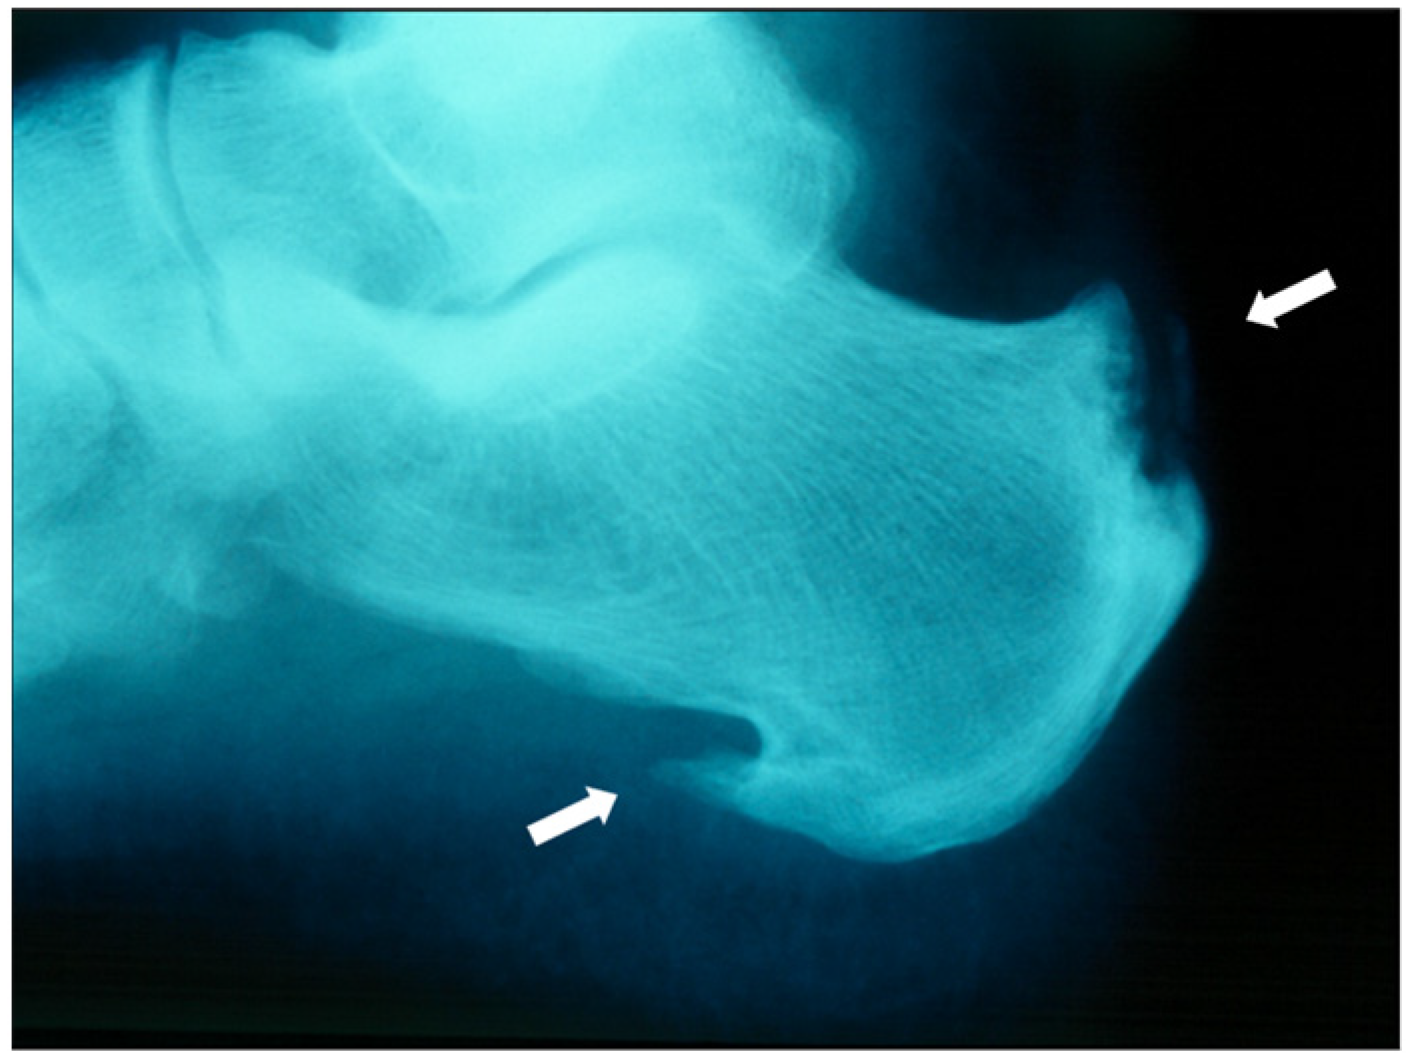

7.2.1. Plain Radiographs